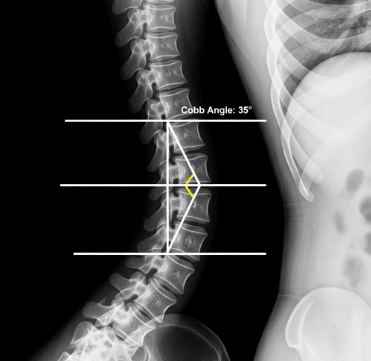

2. X-ray 촬영 (가장 중요!)

전신 척추 X-ray를 찍어 Cobb 각도를 측정합니다. 이 각도가 10도 이상이면 척추 측만증으로 진단됩니다.

• 10~25도: 경도

• 25~40도: 중등도

• 40도 이상: 중증